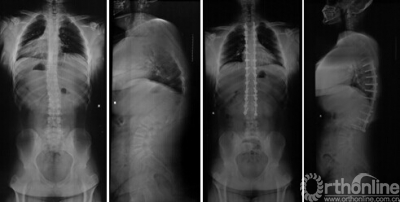

8岁男性患儿,先天性脊柱侧弯(半椎体畸形), 行半椎体切除,术前术后X线片对比